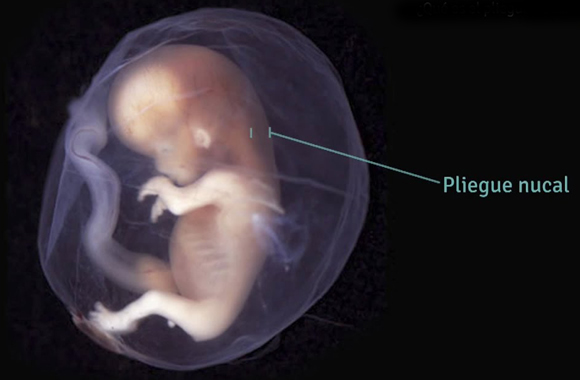

Es un examen que mide el engrosamiento del pliegue de la nuca. Esta es un área de tejido en la parte posterior del cuello de un feto.

Medir este engrosamiento, junto a la detección de la presencia del hueso de la nariz, sumando el flujo de la válvula tricúspidea y el ductus venoso, se coloca en una tabla internacional (Medicine Foundation) que ayuda a evaluar el riesgo para síndrome de Down y otros problemas genéticos en el bebé.

La translucencia nucal es una ecografía obstétrica, que se realiza a la futura mamá entre las semanas 11 y 14. El principal objetivo de este examen es detectar posibles enfermedades cromosómicas, cardíacas, linfáticas y otras.